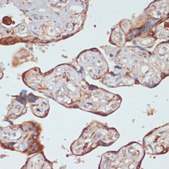

SAB5700630

Anti-Caspase 9 antibody produced in rabbit

Application:

technique(s)

immunofluorescence: 1:50-1:200, immunohistochemistry: 1:50-1:200, western blot: 1:500-1:2000